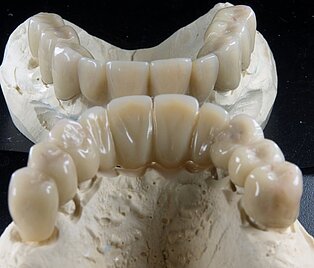

Meisterarbeit von Peter Dengel